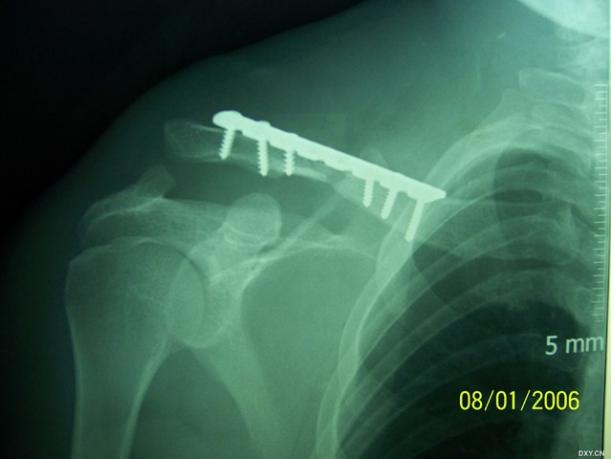

锁骨骨折大家一定都觉得很简单,但锁骨骨折也有一个并不少见的坑,看看下面的病例:

这个锁骨骨折简单吗?简单!做不就完了吗?

做完了,骨折解剖复位漂亮吧?干得漂亮!等等!怎么肩锁关节脱位了 ……

这个锁骨骨折简单吗?另一位网友分享:

等下,拍个双侧对比看看,锁骨骨折合并肩锁关节脱位,还好术前发现了 ……

6.8% 的锁骨中段骨折患者伴有同侧肩锁关节脱位。这个坑也不能踩啊!